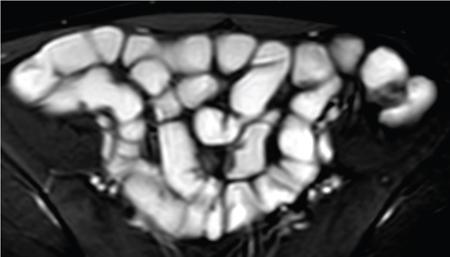

SMALL BOWEL IMAGING Poonam Narang, Himanshu Gupta The small bowel is a long tubular hollow abdominal viscus thrown into intricate folds and loops and packed into the abdominal cavity. It is approximately 5–7 m in length and extends from the gastric pylorus up to the ileo-caecal valve. It is anatomically divided into three parts: duodenum (meaning ‘in twelves’ as its length is roughly equal to the width of 12 fingers), jejunum (meaning ‘fasting’ as it was usually found empty after death) and ileum. The duodenum measures 20–25 cm in length and extends from gastric pylorus to the ligament of Trietz. It is a fixed ‘C’-shaped structure that cradles pancreatic head in its concavity. First part of the duodenum is a triangular conical structure with its base communicating with gastric antrum. Its apex points to the right and cranially, in close apposition with the gall bladder and the under surface of the liver. Second part of duodenum is almost vertical, lying in the right paravertebral gutter. The common bile duct courses obliquely posterior to it and drains at a papilla at its medial wall (the Ampula of Vater), after joining with the main pancreatic duct. Third part is horizontal, crossing the midline between the superior mesenteric artery (SMA) and aorta from right to left, caudal to pancreatic neck. Fourth part is again almost vertical, ascending left of the spine almost to the level of duodenal bulb and transitions to jejunum at duodenojejunal (DJ) flexure. Duodenum is mostly a retroperitoneal structure while the rest of the small bowel acquires a mesentery at the DJ flexure. The jejunum and ileum are intraperitoneal structures, suspended in the abdominal cavity from the posterior abdominal wall by the free end of their ‘fan-shaped’ mesentery and are thus relatively mobile. Though considered a part of small bowel, duodenum differs from the rest of the small bowel in structure as well as function. Plethora of the diseases that affect duodenum are distinct. Peptic ulcer disease affecting the first part does not affect the rest of the small bowel. Most other diseases affecting the duodenum arise from the surrounding structures like pancreas, gall bladder, bile duct, liver and the hepatic flexure of colon. Hence, on imaging, duodenal abnormalities should prompt a search for pathologies of the surrounding organs. While duodenum is structurally a distinct segment, the structural transition from jejunum to ileum is seamless, with no external demarcating point. Histologically, and also on imaging, all three segments have clear identities. Their mucosal lining, folds and presence of submucosal lymphoid follicles are allocated in accordance with their specific functions. Jejunal loops occupy left hemiabdomen and ileal loops, with ileo-caecal junction, lie in the right lower abdomen. Jejunum is about two-fifths of the length of the small bowel, and the ilium forms the rest of the three-fifths of the entire 5–7 m. ‘Terminal ileum’ is a term arbitrarily but commonly used in clinical practice to denote the portion of ileum just proximal to ileo-caecal junction harbouring abundant lymphoid tissue in its walls and playing host to a number of pathologies. At ileo-caecal junction, the ileum joins the caecum obliquely. A valve-like mucosal fold regulates the flow of digested food into the colon and prevents its reflux back. Its efficiency in preventing reflux is quite inconsistent in a large percentage of subjects. The arterial supply of the duodenum is by the branches of hepatic artery (branch of Celiac Axis artery), till the proximal half of second segment (marked by the Ampula of Vater); and by branches of the superior mesenteric artery beyond that point. Duodenal branches of respective superior and inferior pancreatico-duodenal arteries make an arcade along the medial margin of duodenum in the pancreatico-duodenal groove. The rest of the small bowel is supplied by the superior mesenteric artery and its branches while venous drainage is via superior mesenteric vein and its tributaries. These vessels traverse the mesentery, between the twofolds of the peritoneum from the posterior abdominal wall to reach the small bowel forming multiple arcades of vessels within the mesentery. Straight arteries, called the Vasa Recta, arise from the terminal arcade and enter the bowel wall, along its mesenteric border. Disease processes involving the specific artery affects the respective bowel segment that it supplies. Ischaemia, infarction and haemorrhage can be attributed to and localized correctly based on the relevant vascular anatomy. Inflammatory diseases cause engorgement of Vasa recta; and at times, identifying them as a lead point, one is able to localize the involved bowel segment correctly. Vascular ischaemia affects the antimesenteric part of the bowel earlier in the course of the disease. Therapeutic procedures too can be appropriately planned based on the vascular territory of the affected bowel segment. The mesentery forms a fan-shaped suspensory support, tethering the small bowel to the posterior abdominal wall, along a line running obliquely from ligament of Trietz (in LUQ) to ileo-caecal junction close to superior part of right sacro-iliac joint (in RLQ). This ‘root of mesentery’ averages about 15–20 cm in length. It is closely wrapped around small bowel loops and merges with the serosa. All lymphatic and vascular channels supplying to and draining from the small bowel traverse within the mesentery. Thus, pathology originating in one often affects the other by contiguity, haemodynamic alteration or haemo-lymphatic spread. The normal mesentery sandwiches a layer of fat between its two leaves. On imaging, it provides a good background against which identification of pathologies of fluid density (oedema) or soft tissue density (phlegmon, lymph nodes, masses) can be made. Mesenteric oedema often becomes the smoke leading up to the fire, for example: focal oedema adjacent to the site of an otherwise invisible bowel wall perforation. On ultrasound, such tell-tale inflammation is seen as an increase in the echogenicity of mesenteric fat adjacent to the site of bowel pathology. On CT, the hypodense fat becomes hyperdense whenever any pathological change occurs. Delineation of mesenteric vessels is also facilitated due to surrounding hypodense fat. Engorged Vasa recta are easy to identify on imaging as they stand out against the surrounding fat in the mesentery. Similar imaging findings can be extrapolated to MR as well. Similar to the rest of the gastrointestinal tract, the small bowel wall comprises four layers (strata) – from within outwards being mucosa, submucosa, muscularis propria and serosa. Mucosal folds (Valvulae Conniventes) and further finger-like projections of mucosa (Villi) help dramatically increase the surface area for absorption. Only valvulae conniventes are seen radiologically as concentric rings measuring 2–3 mm. The bowel wall measures 1–2 mm when distended and 2–3 mm when collapsed symmetrically in its entire circumference. Increased bowel wall thickness (in the background of adequate luminal distension) is a commonly used marker of pathology. Understanding how different pathologies target specific sites within the micro-structure of bowel wall, along with length of bowel involvement, could be helpful in drawing conclusion regarding the etiopathogenesis. For example, short segmental disruption of the entire thickness of bowel wall favours a unifocal, infiltrative pathology-like malignancy. Long segment submucosal oedema with preserved mucosal integrity/enhancement may be a haemodynamic phenomenon as in portal enteropathy or reactive as in infective enteritis. Depth and invasiveness of a disease process can be monitored for activity/progression, especially on imaging modalities like ultrasonography and MRI. The innermost anatomic layer of small bowel wall, its mucosa forms the absorptive surface which transports nutrients from the lumen into blood/lymph. Pathologies affecting the mucosa cause reduction (shortening) in the available area of absorption – the so-called short bowel syndrome. A variety of metabolic derangements can accompany the nutritional deficiencies caused thereby. Many other inflammatory and infiltrative diseases like lymphomas cause various alterations in the appearances of mucosal folds. Reduction, blunting, flattening, thickening, clubbing, nodularity, polypoid formation, etc. are various imaging appearances of the disease processes affecting the mucosal surface (Figs. 8.3.1.1–8.3.1.3). These abnormalities can be local, segmental, regional or generalized; involving the entire circumference, mesenteric or antimesenteric regions. The radiologist’s role thus lies in identifying the presence, location and extent of mucosal abnormality in addition to suggesting a possible aetiology based on the specific clinical settings. Small bowel has no sensory or motor nerve supply and is regulated by autonomic nervous system for its motility, secretions and absorption. Branches from vagus nerves and from dorsal sympathetic ganglion also traverse the mesentery to innervate the bowel wall at the mesenteric border. During the third week of intrauterine life, the process of ‘gastrulation’ results in formation of three basic layers, namely ectoderm, mesoderm and endoderm, which eventually evolve and differentiate into tissues and organs of all systems. Bowel, along with hepatobiliary and pancreatic system, develops from the ‘primitive gut tube’ that is formed when the endoderm folds upon itself. It then differentiates into three sections: foregut, midgut and hindgut. By 4–6 weeks, the rapidly growing intraabdominal organs outgrow the coelomic cavity. The midgut undergoes physiological umbilical herniation and rotation and then herniates back into the abdomen by the 10th week. Subsequently, the developed midgut organs undergo peritoneal incorporation and fixation to occupy their respective intraabdominal positions. This process takes place in three stages, and interruption at each stage results in specific anomalies of malrotation and peritoneal fixation. During the first stage, from week 6 to week 10, the midgut herniates ventrally into the umbilical cord in a vertical loop configuration. This loop has the superior mesenteric artery in the centre dividing the midgut into a prearterial (jejuno-ileal) segment superiorly and a postarterial (caeco-colic) segment inferiorly. This loop rotates 90 degree counter-clockwise, with superior mesenteric artery as its axis. The prearterial segment comes to lie to the right and the postarterial segment to the left in a horizontal plane. The second stage, from week 10 to week 12, results in a further 90-degree counter-clockwise rotation, and the small bowel loops now are positioned under the postarterial segment. By the end of the 10th week, the abdominal cavity grows large enough to accommodate the entire length of the foetal bowel. As the bowel loops now return to the abdominal cavity, the small bowel returns first followed by the large bowel. Subsequently, the small bowel loops make their final 90-degree counter-clockwise rotation, bringing the D-J junction to the left of the spine, while the colon makes a 180-degree rotation in the same direction to place the caecum in the right lower quadrant of the abdomen. Thus, by the end of stage II, the midgut derivatives have undergone a total 270-degree rotation (including the initial 90-degree rotation) with DJ junction to the left of midline, caecum in the right lower quadrant and transverse colon crossing in front of the duodeno-jejunal junction. Vitello-intestinal duct (VID) gets obliterated by the ninth week. The third stage (from 12 weeks until term) involves fixation of the mesenteries to the posterior abdomen. The completed normal rotation of the bowel produces a long mesenteric attachment for small bowel, extending from ligament of Treitz at the D-J junction in left upper quadrant to the ileo-caecal valve in right inferior quadrant known as the ‘root of mesentery’. The dorsal mesentery of some portions of the gut, like pancreas, duodenum, ascending and descending colon, becomes incorporated into the posterior abdominal wall, making these segments secondarily retroperitoneal (Figs. 8.3.1.4–8.3.1.6). Understanding of chronological embryology helps one to interpret respective imaging features of developmental anomalies and also to look for their associations. During imaging of a suspected case of malrotation, position of DJ flexure, ileo-caecal junction, relative location of jejunal and ileal loops and relation of superior mesenteric artery to the accompanying vein help in reaching the correct conclusion. It should be kept in mind that certain diseases (notably the celiac disease and other malabsorption syndromes) may invert the imaging morphology of jejunum and ileum leading to erroneous diagnosis. Evaluation of orientation of superior mesenteric vessels and the duodeno-jejunal junction would help resolve any ambiguity in such cases (Figs. 8.3.1.7 and 8.3.1.8). Developmental malrotation is often a precursor to small bowel volvulus, or obstruction by extrinsic bands in neonates and infants. In adults, on the other hand, often the malrotations are by themselves, asymptomatic. They get identified only incidentally, or while looking for symptoms due to their associations. Preduodenal peritoneal bands, commonly called as the Ladd’s bands, causing external compressions resulting in bowel obstruction are less common. Often, peritoneal fenestrations and deep fossae, associated with developmental midgut malrotations, present with internal bowel herniations like various para-duodenal and mesenteric herniations. One must be aware of their associations, so as to make the correct interpretation. Internal hernias may be a cause of intermittent postprandial abdominal pain, when reducible; or may result in acute bowel obstruction. They are identified by abnormal location and clumping together of the relatively mobile small bowel loops. High degree of suspicion and knowledge about their locations, helps one to diagnose them with more confidence. Occasionally, constrictions at the neck of hernia can also be identified. Fluoroscopic examination, with palpation to separate the opacified loops, provides the most confident method of their identification. The origin of clinical abdominal radiography dates back to 1896–97, soon after the discovery of X-rays by Wilhelm Roentgen in 1895, when E. Lindemann used X-rays to demonstrate gastroptosis and Walter B. Cannon used them to describe basic physiology of swallowing and peristalsis. The biggest shortcoming with plain abdominal radiographs was lack of inherent contrast with only occasional visualization of air-filled stomach. H. Rieder introduced the concept of contrast abdominal radiographs by giving patients large amounts of radio-opaque bismuth orally, followed by rapid serial abdominal radiographs for better luminal visualization. Later, C. Bachem and H. Gunther introduced barium as inert and nontoxic contrast agent for gastrointestinal imaging. Since their inception, conventional imaging techniques, like plain abdominal radiograph, fluoroscopy and single contrast barium studies, formed the cornerstone of abdominal imaging despite their limitations. In the mid-20th century, with the availability of better barium preparations and advancements in fluoroscopy and radiographic equipment, such as tilt tables, better films and image intensifiers, double contrast barium studies became the problem-solving technique due to its unparalleled ability to image gastrointestinal mucosa meticulously. This enabled the mucosal morphology to be imaged in detail, thus aiding detection of even minute mucosal lesions such as small ulcerations and early carcinomas. With the invention of flexible endoscopes in the late 20th century, UGI endoscopy and colonoscopy replaced abdominal radiography as the frontline investigation for evaluation of the upper GI tract (oesophagus, stomach and duodenum) and colon, respectively, with added advantage of direct lesion visualization and obtaining biopsy. Owing to its length and complex folded anatomy, small bowel is still inaccessible via flexible endoscopes except for a few centimetres of proximal jejunum and terminal ileum. One of the major drawbacks of barium studies and endoscopy was that they provided solely luminal details with lack of information about mural and extramural structures. This ushered the era of modern imaging modalities with cross-sectional capabilities like US, CT and MR. With ongoing advancements in equipment, imaging techniques and contrast media, these modalities are at the forefront of the modern GI imaging, offering better and detailed answers to clinical questions being asked. With recent introduction of capsule endoscopy, gastroenterologists are trying to find a place in noninvasive evaluation of small bowel, but it still has a long way to go. Till then, small bowel evaluation continues to be the radiologist’s domain. Imaging of the small bowel has traditionally played an important role in clinching a diagnosis due to its relative inaccessibility for direct endoscopy. Even with the advent of capsule endoscopy for mucosal evaluation, imaging retains its position in the diagnostic algorithm for its ability to evaluate full thickness of bowel wall and extraluminal structures, in addition to providing information regarding its lumen. Imaging also provides information about the bowel motility, directly or indirectly. Ultrasound and fluoroscopy provide real time visualization of peristalsis. CT scan with oral contrast may be used to monitor transit in certain specific situations, for example in postoperative settings, to differentiate paralytic ileus from mechanical obstruction. Small bowel anatomy as well as pathology can be assessed and compared on various imaging modalities under the following headings: Plain abdominal radiographs have a limited role in modern small bowel imaging. It gives relatively little diagnostic yield, and most modern departments have easy availability of US, CT and MRI. In setting of acute abdomen, plain abdominal radiographs have greatest value in evaluation of pneumoperitoneum; gas patterns and air-fluid levels in bowel obstruction; enteroliths; radio-opaque foreign bodies; and to a limited extent, in the evaluation of bowel wall pattern in cases of bowel ischaemia/colitis. A good supine abdominal radiograph helps to evaluate gas pattern and bowel calibre. The kilo-voltage should be low, preferably 60–75 kV, to maximize contrast. Exposure time must be short to minimize motion blur. It should cover the entire abdomen from domes of diaphragm to the inferior border of pubic symphysis, including obturator foramina (hernial orifices). The X-ray beam should be centred at the level of iliac crests with proper collimation. An adequate erect abdominal radiograph should suffice to demonstrate air-fluid levels and free peritoneal gas in cases of pneumoperitoneum, with erect chest x-ray (CXR), and left lateral decubitus radiographs being reserved for suspicious cases of small pneumoperitoneum. It is advisable to keep the patient in an erect position for at least 10–12 minutes before taking erect CXR or erect abdominal radiograph and in left lateral decubitus position before taking left lateral decubitus radiograph to allow free air time to rise to the highest point. Erect chest radiographs are more sensitive and reliable due to better visualization of free air forming sharp margins with diaphragm and liver surface, respectively. Normally, small amount of intraluminal gas is seen in nondilated small bowel loops. Three or more air-fluid levels measuring more than 2.5 cm in width are abnormal for small bowel and indicate stasis. Increased aerophagia or laboured breathing may sometimes give a peculiar appearance on radiographs called as ‘meteorism’. The small bowel loops appear distended with air, mimicking stasis. However, due to minimal fluid content, no abnormal air-fluid level is seen on accompanying erect radiographs. However, it is now recognized that the number, distribution and length of air-fluid levels on erect abdominal radiograph cannot reliably differentiate between obstruction and ileus and can be often misleading (Figs. 8.3.1.9 and 8.3.1.10). It must be mentioned here that plain X-ray abdomen has retained its popularity in healthcare settings that lack modern infrastructure like CT scanner in the Emergency Department. A rapid, low-dose CT scan of the abdomen gives much more information with higher degree of confidence as compared with that provided by a set of plain radiographs. Barring the cost and availability, low-dose noncontrast CT scan should replace plain radiography in patients presenting with acute abdomen. The earliest enteric contrast media used in GI tract imaging was iodized oil (Lipiodol). However, due to its oily nature, it did not coat the mucosa. At present, medical grade bismuth sulphate is the contrast media of choice for GI imaging. The reasons for using barium sulphate are: Barium studies have been the most reliable conventional techniques in small bowel imaging since their inception and still remain unmatched in detecting luminal dilatation or narrowing, subtle mucosal alterations and motility disorders. One of the major inherent limitation of conventional barium studies is the lack of information regarding extraluminal/extraintestinal structures. Duodenum is usually studied along with the stomach, using high-density barium suspension. Single or double contrast technique can be used, depending on the information sought. Only in cases where duodenal obstruction, diverticulum, fistula or leak needs to be demonstrated, a single contrast study using barium or gastrografin (in suspected cases of peritoneal leak) is performed. Double contrast studies require special manoeuvres to distend the lumen with air after coating the mucosa with a layer of barium. The patient is positioned in right or left lateral- oblique position, and images are taken under flouroscopic view to demonstrate barium coated, distended and then a collapsed duodenal bulb; and C loop till the DJ flexure. Duodenal ulcers usually deform and contract the symmetrical and conical duodenal bulb. Strictures or focal narrowing of the second part of duodenum can be due to congenital or inflammatory diseases. Widening of C loop indirectly reflects enlargement of pancreatic head. A small or large diverticulum along its medial wall adjacent to Ampula of Vater is seen in many subjects and is mostly incidental. Mucosal folds of the duodenum, seen in relief, can demonstrate focal or regional inflammatory/infiltrative processes. For fluoroscopic barium studies of the jejunum and ileum, a large amount (500–600 mL) of thinner suspension of barium sulphate is given orally; and flouroscopic images with local compression are taken at intervals of 20–30 minutes, till most of the barium reaches and distends the caecum; and ileo-caecal junction is demonstrated. To improve visualization of the ICJ, caecum can be insufflated with per-rectal air. This technique is called as per-oral pneumocolon and is mostly used in countries where diseases like tuberculosis that involve the ICJ are common. Enteroclysis too can be performed to better visualize the small bowel without opacifying the stomach and duodenum. The technique also achieves a continuous, unbroken column of barium without segmentation caused by intermittent gastric emptying. A nasogastric tube of 10F is introduced over a guidewire, to position its tip just beyond the ligament of Trietz. About 1200–1500 mL of barium is pumped manually, or by an automated pump under fluoroscopic vision to opacify the entire small bowel. It may be followed by 0.5% methyl cellulose if a double contrast study is desired. The rate of instillation is roughly 80 mL/minute but is titrated under vision so as to obtain adequate distension without causing the column to break or inducing bowel atony. Multiple supine and oblique views are obtained with compression to separate out the overlapping bowel loops. The procedure is long and entails a large amount of radiation exposure, while providing limited information about the lumen, extrinsic impressions and displacements only. At present, its best use is in demonstrating postoperative small bowel obstruction and in resolving some cases where cross-sectional imaging is ambiguous in demonstrating partial obstructive lesions. The above description is now more for its historical value, though the technique is still practised in less-privileged departments across the world. Endoscopic studies have largely replaced barium studies of the duodenum; while cross-sectional imaging has taken over the prime status in imaging of the jejunum and ileum. With conventional fluoroscopic studies and CT enterography dominating the field of small bowel imaging, ultrasonography (US) has been an underrated diagnostic imaging tool in evaluating bowel pathologies up till now, with its role limited to diagnosing appendicitis, intussusception and hypertrophic pyloric stenosis. Operator-dependent nature of the modality, technical challenges of imaging a mobile structure and gaseous contents are the major reasons for its relative unpopularity. These factors make bowel US technically challenging and may lead to misinterpretation by less-experienced radiologists. Nevertheless, with constant improvements in US machines, development of technical experience and integration of clinical details for targeted assessment, US can emerge as an indispensable diagnostic tool in evaluating patients with known or suspected small bowel pathology. Conventional transabdominal US, with a 2–6 MHz curvilinear probe, should be performed initially on a fasting patient, with special attention to the region of pain or probe tenderness, to look for any extraintestinal cause that can explain the patient’s symptoms. It can also detect any intraluminal pathologies, thickened bowel loop along with secondary findings such as perienteric inflammation, lymphadenopathy, ascites, collections, masses and hepatic metastatic lesions in cases of suspected bowel malignancies. This is followed by high-frequency (5–15 MHz) assessment of nondistended bowel using linear probes in either bowel or neonatal abdomen presets. Some authors recommend using 4–10 MHz curvilinear array initially, followed by problem solving 6–12 MHz for good balance between penetration and resolution. Scanning parameters are so optimized that all layers of bowel wall are visualized. Practically it is almost impossible to scan/evaluate the entire length of small bowel by US, thus a quadrant-wise approach is more practical, wherein the abdomen is divided into four equal quadrants by two imaginary perpendicular lines passing through umbilicus. Bowel loops in each quadrant are thoroughly evaluated for any potential abnormality followed by evaluation of the ICJ, terminal ileum and as much part of distal ileum as possible. Use a graded compression technique with gentle sweeping movement of the probe to separate bowel loops and displace intraluminal air. Using optimal sensitivity and doppler settings, colour or power doppler imaging may be used to assess the mural, mesenteric or intralesional vascularity. The bowel under probe should be assessed for motility, mural thickness and gut signature. When viewed at high frequency, normal bowel wall consists of five alternating concentric rings of low and high echogenicity usually called the ‘gut signature’ – innermost lumen-mucosa interface (hyperechoic), thin hypoechoic muscularis mucosa, echogenic submucosa, followed by hypoechoic muscularis propria and outermost echogenic serosa (Fig. 8.3.1.11). US is the only imaging modality that can demonstrate these histological layers of bowel wall distinctly. In various pathological conditions, this gut signature may be preserved, exaggerated, diminished, disrupted or completely lost (Figs. 8.3.1.12 and 8.3.1.13). Disruption of the normal gut signature usually points towards a malignant or infiltrative pathology. Diseased bowel wall must be evaluated for mural and adjacent mesenteric vascularity. Usually in normal bowel wall, the doppler signals are negligible, but with introduction of low-flow imaging software, the operator must be habituated with the appearance of normal bowel vascularity on their US machines. Active inflammation and hypervascular lesions show substantially increased vascularity in the affected bowel segments. On the other hand, thickened bowel loops without doppler signals in wall and adjacent mesentery may indicate ischaemia. Colour doppler imaging may allow differentiation of active mural thickening (increased blood flow) from chronic mural thickening/fibrosis (decreased blood flow). Bowel pathology may extend and involve the perienteric mesentery, adjacent bowel loops or solid organs. One must be vigilant enough to look for mesenteric fat oedema, collection, interbowel free fluid and lymphadenopathy when inflamed bowel segment is visualized. Hydrosonography and sonoenteroclysis are useful techniques in evaluating small bowel on US. Introduction of large volumes of echo-poor liquid oral contrast (water, mannitol, polyethylene glycol, etc.) via either oral route (hydrosonography) or fluoroscopically placed naso-jejunal tube (sonoenteroclysis) results in adequate luminal distension of small bowel loops and displaces the intraluminal gas aiding better bowel visualization. Diagnostic accuracy of sonoenteroclysis is comparable to barium enteroclysis for detecting small bowel lesions. In the past few years, there has been a constant rise in the use of intravenous microbubble US contrast in organs other than the liver. EFSUMB guidelines recommend 2.5–5.0 mL of Sonovue (Bracco Imaging) for contrast-enhanced US of bowel. High-frequency (>7.5 MHz) linear array probes are used for demonstrating the differential enhancement of bowel wall layers. Following intravenous injection of US contrast material, peak arterial enhancement occurs after 30–40 seconds, followed by venous phase lasting from 40 to 120 seconds. High-end US machines can produce dynamic enhancement curves for quantitative analysis by placing region of interest over bowel wall or mass lesions. Real-time imaging capability of US allows for evaluating the bowel motility. Rhythmic, phasic contractions with slow antegrade propulsions are usually seen in the small bowel. Large migratory contractions may occur spontaneously and are usually seen after fasting. Various bowel pathologies tend to alter the rate of peristalsis. Hypoperistalsis is an indicator of unhealthy bowel and can be seen in inflammation, obstruction, ischaemia or infiltrative pathologies. High-grade obstruction usually shows fluid distended bowel loops with nonpropulsive ‘to and fro’ movement of the intraluminal contents. During evaluation of acute abdomen in paediatric patients, some small bowel pathologies get so convincingly diagnosed that this modality deserves a place in their imaging algorithm. Target sign, telescoping bowel sign or doughnut sign of intussusception can guide one to directly treat or further image to look for a lesion at lead point. Colour doppler interrogation can suggest the level of ischaemia in these loops. Similarly, bowel strangulation and ischaemia can be readily identified in a herniated bowel loop. Follow-up of Crohn’s disease for activity is routinely done by colour doppler imaging in departments where sinologists are trained for the job. SMA and celiac axis arteries can be individually interrogated in cases suspected of bowel ischaemia. This is especially useful in cases that are already diagnosed on CTA/MRA and need to be followed up noninvasively. In GI bleeding, USG can diagnose presence of portal hypertension and varices to clinch the diagnosis. A mention of the relative orientation of SMA and superior mesenteric vein (SMV) has already been made in diagnosis in cases of midgut malrotation where the association is found in about 60% of cases. Whirling and twisting of the two is seen in the case of midgut volvulus. In tropical countries, finding ascaris worms within small bowel loops on US is not uncommon. In correct clinical context, this finding can help reach a conclusive diagnosis. Endoscopic US (EUS) has rendered the GI tract and surrounding structures acquiescent to US evaluation combining the range of endoscopy with the diagnostic abilities of US. It couples a 5–12 MHz US probe with an endoscope. There are two types of echo-endoscopes: radial and linear. Radial echo-endoscopes are used in high-resolution diagnostic imaging, as they provide a 360-degree view that most operators are familiar with. Linear echo-endoscopes have limited field of view but are equipped with therapeutic-working channel facilitating image-guided tissue sampling and intervention. The proximity and high resolution of EUS allow a detailed image-based analysis of lesions in and around the accessible GI tract. The technique is best suited for hepatobiliary and pancreatic evaluation where they are apposed to the bowel wall. In small bowel imaging, their utility is limited to the duodenum and proximal jejunum. EUS can depict about nine distinct layers of bowel wall, as against the abdominal US which has a capability of resolving up to five layers. Identification of the involved layers can aid in differentiating ulcerative colitis from Crohn’s disease in selected patients. This also helps in improved analysis of tumour penetration and hence the ‘T’ staging. Submucosal tumours can be differentiated from extraintestinal indentations, and they can further be characterized as solid, cystic or vascular lesions (Fig. 8.3.1.14). Peri-lesional infiltration and nodes can be accurately assessed. Malignant GIST (gastrointestinal stromal tumor) can be differentiated from benign ones on follow-up, by their size (>3 cm), irregular margins and heterogeneity of echotexture. Identification of peri-lesional nodes permits accurate nodal staging and is useful during follow-up. The increasing demand to shift from invasive or surgical interventions to minimally invasive alternatives has driven the development of multiple EUS-guided interventions, and EUS-guided tissue sampling is perhaps the most useful contribution of this technique. EUS-guided endoscopic resection can also be done for mucosal tumours. The technique requires training and familiarity with the orientation and is usually the domain of the endoscopists. Other limitations of EUS remain the availability of the technique and the shallow depth of field of view. Cross-sectional imaging has now become the mainstay of bowel imaging as they allow visualization of the entire bowel along with luminal, mural and extramural manifestations in a single examination. With recent advancements, like superior detectors, thinner collimation and reduced scan time, MDCT (multi-detector computed tomography) has now emerged as the first line investigation for most bowel conditions because of its wide availability, rapid execution, superb spatial and temporal resolution and high-quality multiplanar reconstructions. Modern postprocessing techniques, such as volume-rendered images, shaded surface displays, virtual enteroscopy and the introduction of artificial intelligence (computer-aided detection) have increased the sensitivity of CT and enhanced the confidence of radiologists in picking up smaller lesions with greater accuracy. However, like any other imaging technique, CT has its fair share of drawbacks. High-radiation dose that CT entails is of significant concern especially in young patients or patients with chronic bowel conditions who would require multiple serial scans during their treatment course. Other demerit is poor mucosal delineation and subtle alterations in mucosal morphology, which are best demonstrated on barium studies. Types of enteric contrast agents: (Table 8.3.1.3). Collapsed bowel loops may give false impression of bowel wall thickening, thus mimicking pathologies or may hide one. Enteric contrast agents are necessary to adequately distend, otherwise, usually collapsed bowel loops, for better evaluation. Choice of enteric contrast agent depends on the information being sought. Neutral enteric contrast agents, with their inherent low CT attenuation (0–30 HU), provide better evaluation of mucosal, submucosal pathologies and bowel wall enhancement patterns and are best for routine CT enterography/enteroclysis. Positive agents, due to their high CT attenuation, obscure GI bleeds, mucosal and mural details. They have fewer indications; that is in evaluation of site of small mechanical obstruction, bowel perforation, anastomotic leaks, sinus/fistula patency, differentiating bowel from adjacent masses, interloop collections or lymphadenopathy. Negative contrast agents like carbon dioxide are being used in virtual enteroscopy. Water as enteric contrast agent is cheap, easily available, can be consumed in large quantities and better tolerated; however, due to its rapid intestinal absorption, distension achieved by water is highly variable and sometimes inadequate. Better bowel distension is achieved by mannitol and methylcellulose as they retain water in bowel lumen. Milk as neutral contrast is preferred in paediatric patients as hyperosmolar agents like mannitol can cause dehydration. PEG can cause watery diarrhoea in some patients. Commercially available neutral agent, VoLumen (Bracco Diagnostics, Princeton, NJ) is a 0.1% w/v barium sulphate suspension in sorbitol and produces better distension than many other neutral agents. Usually 1–2 L of oral contrast produce adequate luminal distension; however, volume to be administered should be adequately tailored according to the safety profile of the specific agent, to achieve good luminal distension with minimal side effects. Smaller volumes, depending upon patient tolerance, are recommended in patients with history of bowel resection. Patients are advised to completely restrict solid food intake for about 6 hours prior to examination. To assure better compliance, they should be well-briefed about the procedure. They are encouraged to drink at least 1.3–1.5 L of neutral oral contrast over a period of 45–60 minutes immediately prior to the study. An intravenous assess is secured with 18G or 20G cannula and saline flush is given to check patency. Slow injection of 1 mL of Buscopan (hyoscine butylbromide) is given immediately before the scan to relax bowel smooth muscles and decrease peristalsis. Scan techniques include routine plain and ‘enteric phase’ imaging performed 45–50 seconds after giving ~1.5–2 mL/kg of iso or low osmolar intravenous contrast at the rate of 4 mL/s. Multiphase CT with arterial and delayed phases is indicated while evaluating occult GI bleeds or vascular malformations. Slice thickness of 0.9 mm is adequate with reconstruction interval of 0.45 mm. CT enteroclysis is a semiinvasive imaging technique that differs from CT enterography only in the mode of enteric contrast administration. CT image acquisition remains the same. It combines the advantages of enteroclysis (good luminal distension) with cross-sectional imaging in a single examination. Large volume of enteric contrast is pumped directly into the small bowel at high rates. This volume challenge to bowel ensures better and reliable luminal distension than CT enterography, thus aiding in better evaluation of mucosal lesion and mural enhancement patterns. A good CT enterography examination with adequately distended bowel loops can demonstrate luminal, mural as well as extraluminal pathologies. Better patient tolerance and noninvasive nature has made CT enterography a preferred imaging choice in modern noninvasive small bowel evaluation. A good CT examination of the bowel can help in detecting abnormal bowel loops positioning, intussusception (Fig. 8.3.1.15), intraluminal, mural (Figs. 8.3.1.16 and 8.3.1.17) and extramural pathologies. Arterial phase images are particularly useful in evaluating the small bowel arterial supply for stenosis, strictures, thrombosis and arterio-venous malformations (AVMs) (Figs. 8.3.1.18 to 8.3.1.20). Until recently, despite excellent inherent soft tissue resolution, MR imaging had limited role in GI tract evaluation. The major hurdle being longer acquisition time, resulting in image degradation from motion artefacts due to respiratory movements and bowel peristalsis. With advancements in MR hardware and development of faster breath-hold imaging sequences, scan times have reduced considerably with minimal motion artefacts and superior image quality. When combined with good luminal distention and intravenous administration of gadolinium-based contrast media, MR provides exceptional luminal, mural and extramural details along with vascular and functional information. Increasing awareness of radiation hazards associated with high-radiation dose in CT has furthered MR enterography to the forefronts of GI imaging especially when imaging paediatric, pregnant patients or patients with chronic bowel pathologies who require sequential imaging during their disease course. Advantages of MR over CT are lack of ionizing radiation, superior soft tissue contrast, dynamic information with respect to bowel motility and relatively safer intravenous MR contrast profiles. Limitations of MR include limited availability, higher cost, longer scan time, lower spatial and temporal resolution as compared to CT and known contraindications to MR such as claustrophobia, metallic implants and pacemakers. Gadolinium-based contrast agents, especially gadodiamide, are contraindicated in patients of chronic kidney disease or renal insufficiency with eGFR < 30 mL/min/1.73 m2 due to risk of fatal nephrogenic systemic fibrosis. For adequate bowel cleansing, patients are advised to take liquid-based diet for a day with four bisacodyl tablets in the evening prior to imaging. Preprocedural fasting of 4–6 hours is advised. All this minimizes food residue and debris in small bowel which may mimic luminal pathology while interpreting the scan. Bowel distension is necessary for evaluating the intraluminal and mural pathologies as collapsed small bowel segments can mimic pathological mural thickening or hide underlying pathologies. MR imaging of small bowel makes use of enteral contrast agents to provide homogenous and adequate intestinal distension and increase contrast between lumen, bowel wall and extraluminal soft tissue. Properties of a good enteral contrast agent include easy availability, low cost, least side effects and high contrast between lumen and bowel wall. Depending on the signal intensity on various sequences, MR enteric contrast agents can be divided into positive (bright on T1w images), negative (dark on T2w images) and biphasic (dark on T1w and bright on T2w images) contrast agents. Positive contrasts like gadolinium chelates, ferrous and manganese ions and food items like blueberry juice are not commonly used as enteric contrast due to high cost, unavailability and poor distinction of mural enhancement postintravenous contrast injection. Negative contrast agents include superparamagnetic iron oxides (SPIOs) and ultra-small SPIOs (USPIOs). They are used in MR pancreatico-cholangiography to suppress the high signal from bowel luminal contents. High signal intensity of pathology or inflammation in bowel wall and surrounding fat stands out against accompanying luminal low signal intensity on T2W images. However, negative contrasts are not preferred for bowel imaging as, apart from gastrointestinal side effects like nausea, vomiting and diarrhoea, the associated susceptibility artefact can mask the hypointense signal from normal bowel wall and hide low signal intensity lesions like carcinoids on T2W images. Biphasic agents are the most commonly used enteric contrast agents in MR and include osmotic agents like mannitol, polyethylene glycol, low-density barium sulphate (VoLumen) and nonosmotic agents like water, locust gum resin and methylcellulose. Osmotic agents retain water within the lumen producing better luminal distension than nonosmotic agents; however, this may lead to mild diarrhoea postexamination. On T2W images, there is marked contrast between the high signal intensity of the lumen against dark appearing normal bowel wall, thus aiding detection of transmural ulcers, sinuses and fistula. On fat-suppressed postintravenous contrast T1W images, their inherent low signal intensity provides outstanding contrast between low signal intensity lumen, intermediate signal intensity of normal bowel wall and high signal intensity of enhancing mural/extramural inflammation or neoplasm. Enteric contrast may not be required in patients with suspected high-grade obstruction because retained intestinal fluid adequately distends the loops proximal to obstruction, and additionally administering large volumes of fluid may cause patient discomfort, vomiting or even bowel perforation. Similar to CT imaging, MR imaging of the small bowel includes two techniques of small bowel distension: MR enterography (MRE) with oral administration of the enteric contrast and MR enteroclysis, wherein the enteric contrast is infused directly into the small bowel via a naso-jejunal tube inserted under fluoroscopic guidance.

MR imaging of small bowel

Patient preparation and enteric contrast agents